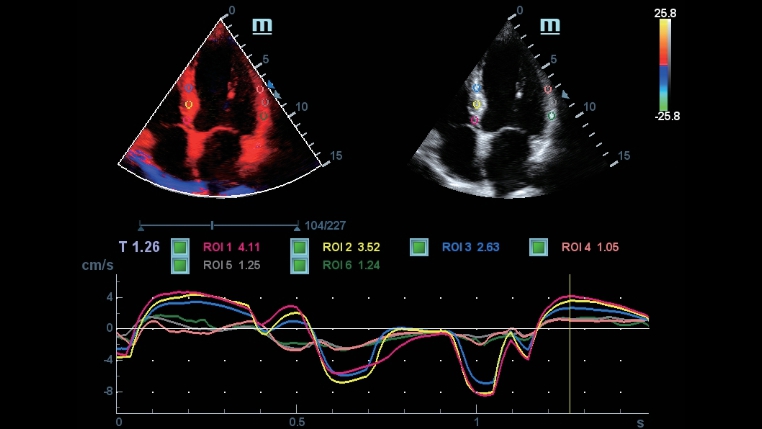

DC-40 mit Full HD bietet viele Tools zur bequemen Maximierung der diagnostischen Genauigkeit. Das DC-40 mit Full HD deckt die allgemeine Bildgebung, die Obstretik/Gyn?kologie sowie die Kardiologie ab und bietet damit eine Komplettl?sung f├╝r die wichtigsten klinischen Bereiche, mit vereinfachtem Workflow f├╝r mehr Effizienz.